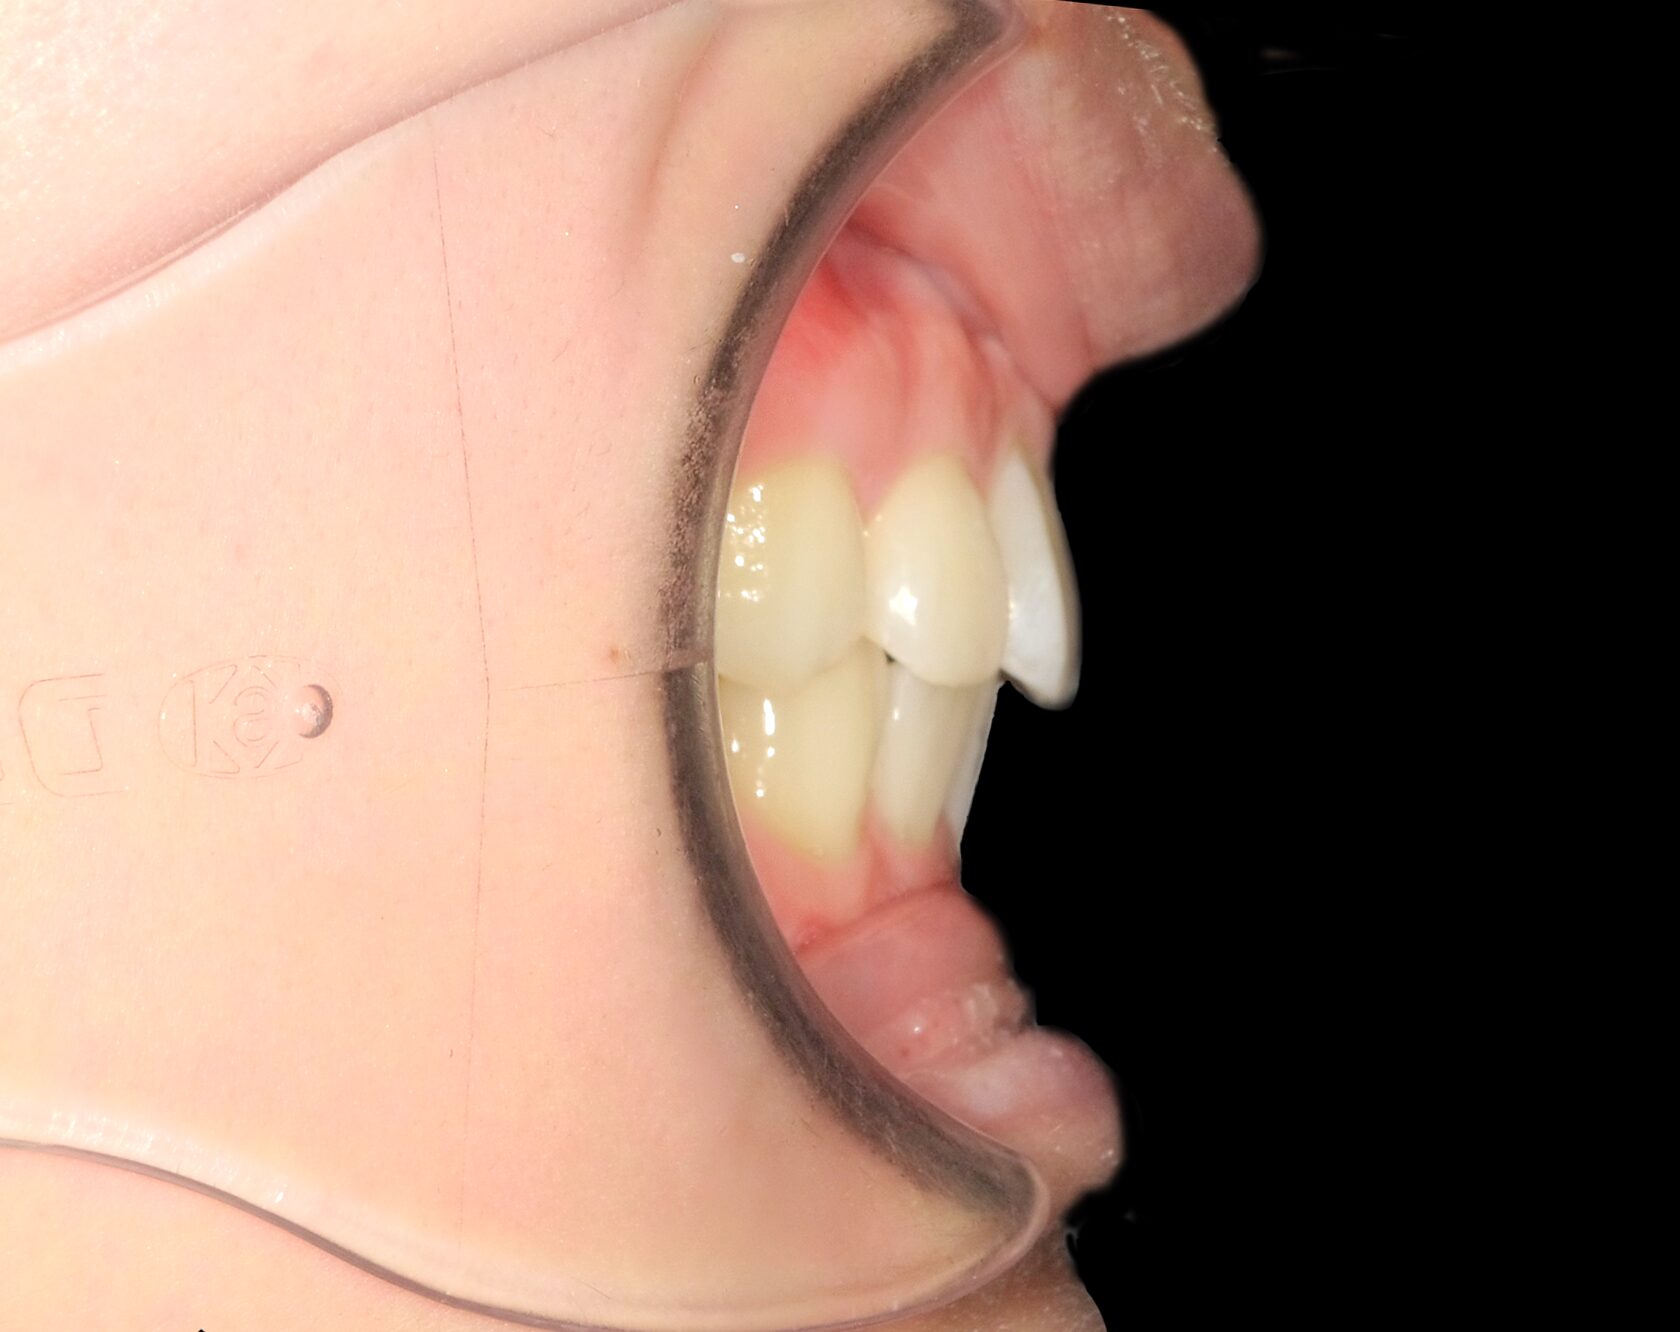

真横から見ると上の前歯が飛び出ています。

真横から見ると、前歯が内側に位置し、出っ歯が改善しています。